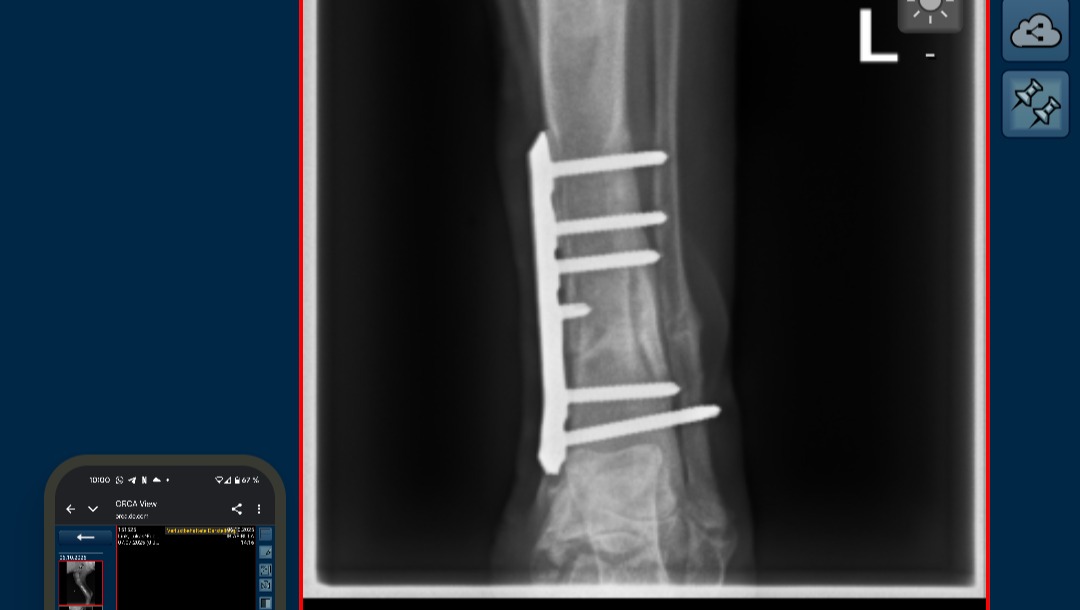

Am folge Tag (19. Sep.) wurde Fuchur in der Tierklinik Wiesloch operiert.

Die OP ist sehr gut verlaufen. Die Bruchstelle wurde mit einer Platte und Schrauben Fixiert.

aktuell ist noch unklar wie sich die Wachstumsfüge unterhalb des Bruches regenerieren wird.

In der dritten Woche nach dem Bruch ist das Wachstum von fuchurs Bein aber glücklicher Weise nach wie vor unaufällig.

Am Montag 06.10. wurden Kontroll-röntgenbilder erstellt und die Fäden gezogen. Der Bruch und die Op Wunde sehen sehr gut aus!!